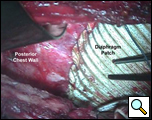

Through a 7th interspace right thoracoabdominal incision, the right lung was decorticated and pneumolysis performed (Figure 5). Once dissection was complete, the liver was found in the pleural space with only a small rim of diaphragm medially (Figure 6). The liver was completely mobilized and reduced into the abdomen, insuring that the right hepatic vein was not kinked. Multiple liver biopsies were obtained. The diaphragm was reconstructed using a 15x25cm 2mm thick polytetrafluoroethylene patch, anchoring it posteriorly near the 10-11th thoracic vertebral level to the posterior mediastinal fascia, laterally around the ribs, and anteriorly to the medial remnant of the diaphragm (Figure 7).